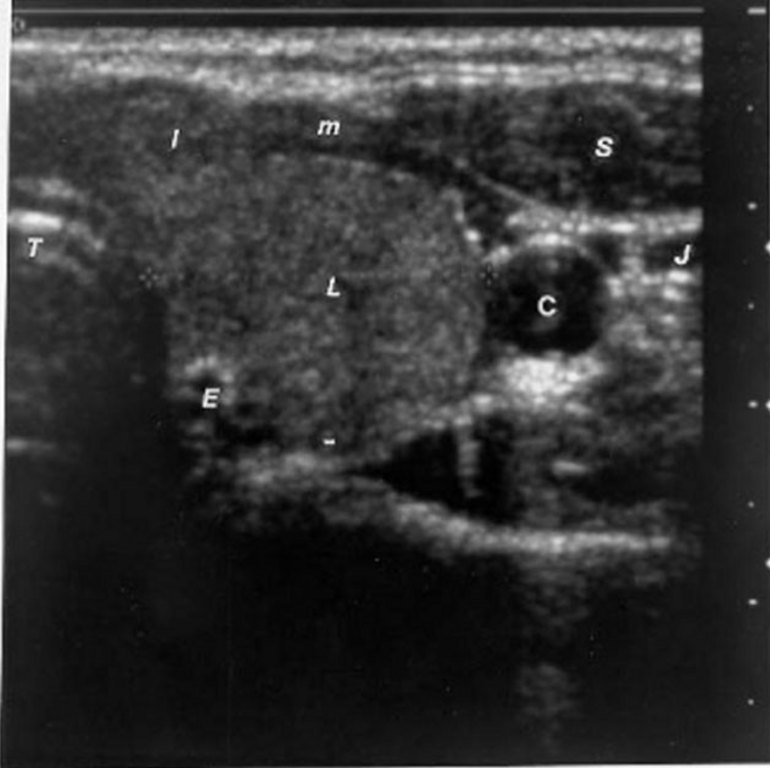

Hashimoto’s Thyroiditis Radiology Key

From radiologykey.com

Hashimoto’s Thyroiditis Radiology Key Thyroid Ultrasound Area A thyroid ultrasound is typically performed to evaluate the thyroid gland, located in the front of the neck. The best place to begin the exam is in the midline directly over the trachea, as it is the easiest landmark to identify by physical exam. A thyroid ultrasound is a safe, painless procedure that uses sound waves to examine the thyroid. Thyroid Ultrasound Area.